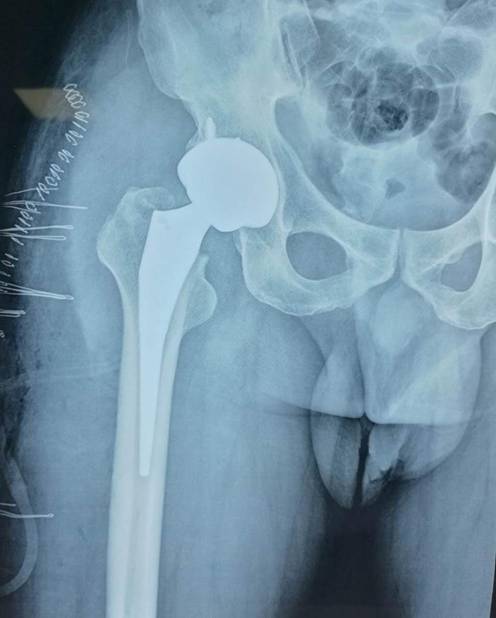

全髋关节置换术治疗股骨头坏死

优点:手术成熟,疗效确切。

微创直接前方入路髋关节置换

优点:不切断任何肌肉,无痛,损伤小,可早下床。

全髋关节翻修术